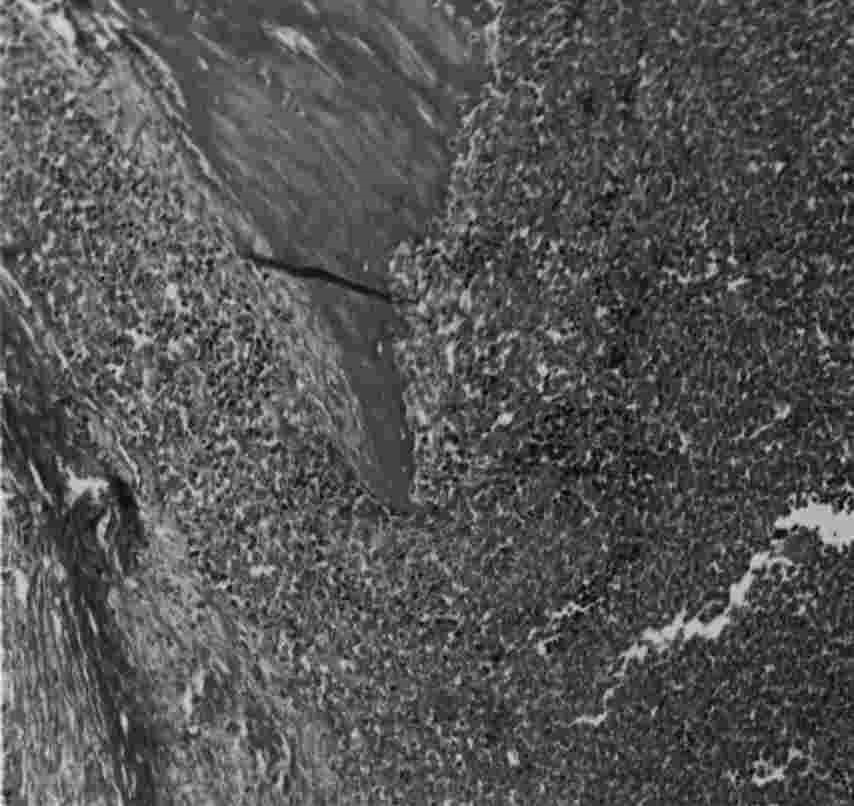

Histology

This is a small round blue cell tumour, which is believed to arise from the endothelial cells in the bone marrow (primitive neurectodermal cell). Macroscopically it is lobulated, grey in colour. Microscopically it has sheets of small dark polyhedral cells, with no regular arrangement and no ground substance.

Low power shows bone surrounded by a highly cellular neoplasm, with the high power showing the sheets of round cells.